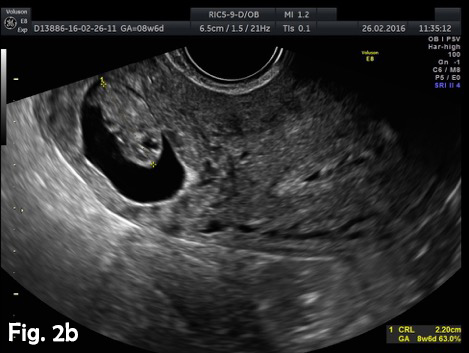

A 39-year-old woman presented for a routine dating scan at 8 weeks 6 days amenorrhea. At examination she also was asymptomatic. Ultrasound examination revealed an empty uterine cavity with a regular endometrium and a gestational sac with a viable embryo located in the interstitial portion of the right fallopian tubes, separate and greater than 1 cm from the lateral edge of the uterine cavity (Fig.2a). The sac was surrounded by a thin myometrial mantle (Fig.2b). Color Doppler sonography revealed peritrophoblastic blood flow around the gestational sac and heart movements (Video 1). No fluid was seen in the pouch of Douglas. Bulging of the outer contour of the uterus in the cornual region was shown on 3D ultrasound (Fig.2c). Laparotomy with excision of the interstitial portion of fallopian tube and right cornual part of the uterus was performed. The postoperative period was uncomplicated.

Figure 2b. A gestational sac with one live embryo (CRL measuring 2.20 cm, corresponding to 8 weeks 6 days amenorrhea) located in right interstitial area.